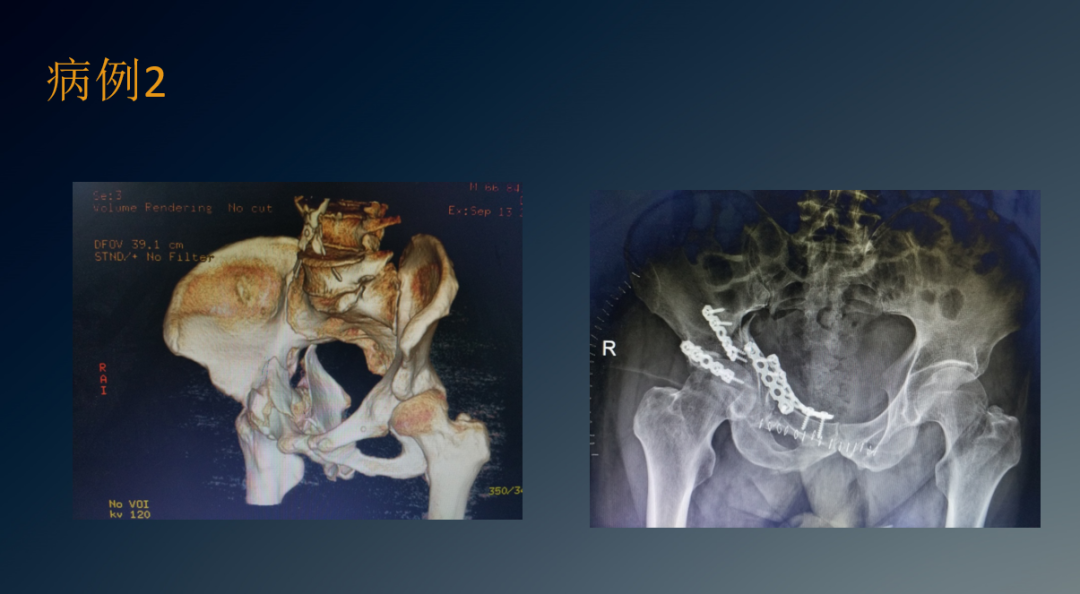

临床病例